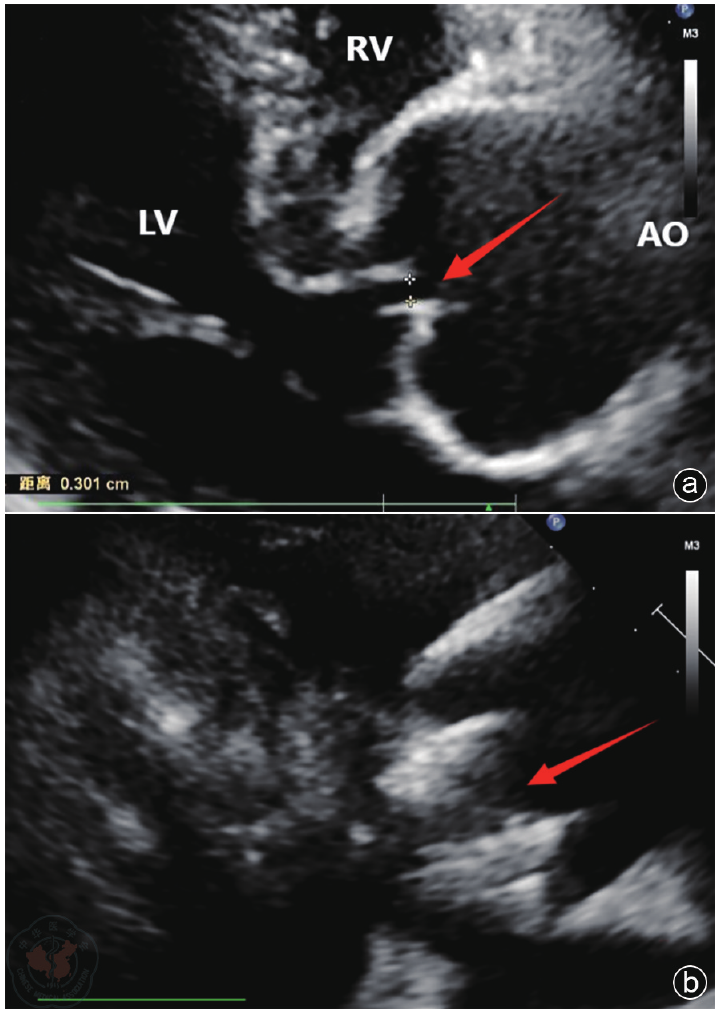

Methods The diagnosis and treatment data of one patient with severe AI admitted to the Air Force Medical Center on October 29, 2025, were retrospectively analyzed. Preoperative echocardiography was used to accurately assess valve structure (including number, morphology, echogenicity, etc.), the cause of regurgitation (including valve calcification, prolapse, perforation, annular dilatation, etc.) and its severity (including the ratio of regurgitant jet width to left ventricular outflow tract width, regurgitant area and length, Doppler spectra, etc.). Key aortic root dimensions were measured (including valve orifice area, aortic annulus, sinus of Valsalva, sinotubular junction, and ascending aortic diameters) to provide a basis for selecting the appropriate J-VALVE TF prosthesis size. Intraoperative ultrasound served as a real-time " navigation" system, guiding the entire process of device delivery and deployment, and providing immediate assessment of prosthesis position, function, and the presence of paravalvular leakage. Postoperative ultrasound served as the primary follow-up tool to evaluate prosthetic valve function and cardiac chamber reverse remodeling.

Results The patient experienced chest tightness and shortness of breath one year prior while lying flat at night. Symptoms could be induced by exertion or insomnia, lasted approximately one minute, and could be relieved by taking a deep breath. Echocardiography indicated: aortic developmental anomaly, aortic valve insufficiency with massive regurgitation, dilatation of the aortic sinus, and widening of the ascending aorta. Based on clinical presentation and echocardiographic findings, the patient underwent TAVR using the J-VALVE TF valve system. Intraoperative ultrasound provided real-time guidance during the delivery and deployment of the J-VALVE TF valve, monitoring the deployment process and the relative position of the delivery system. It was used to assess potential impacts on the mitral valve and coronary ostia before deployment and to evaluate prosthetic valve function after deployment. Postoperative assessment focused on the presence of paravalvular leakage, cardiac function, and the recovery of cardiac chamber geometry.